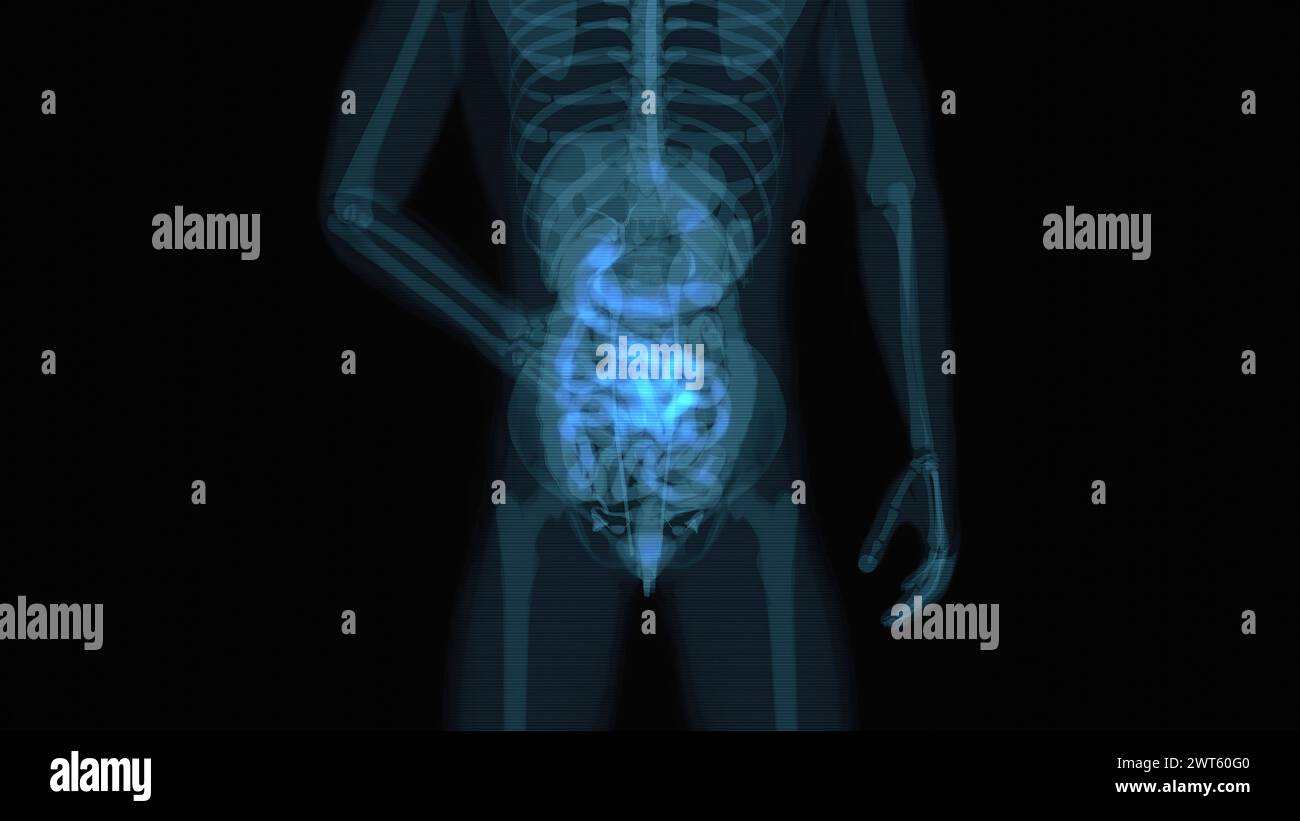

Organes abdominaux et pelviens féminins, illustration. Banque D'Imageshttps://www.alamyimages.fr/image-license-details/?v=1https://www.alamyimages.fr/organes-abdominaux-et-pelviens-feminins-illustration-image600036416.html

Organes abdominaux et pelviens féminins, illustration. Banque D'Imageshttps://www.alamyimages.fr/image-license-details/?v=1https://www.alamyimages.fr/organes-abdominaux-et-pelviens-feminins-illustration-image600036416.htmlRF2WT60G0–Organes abdominaux et pelviens féminins, illustration.